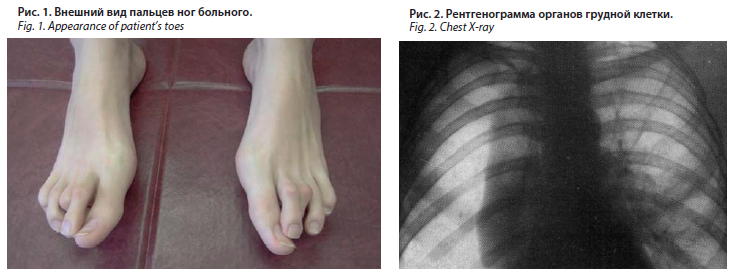

Диагностика плеврального выпота: что нужно знать